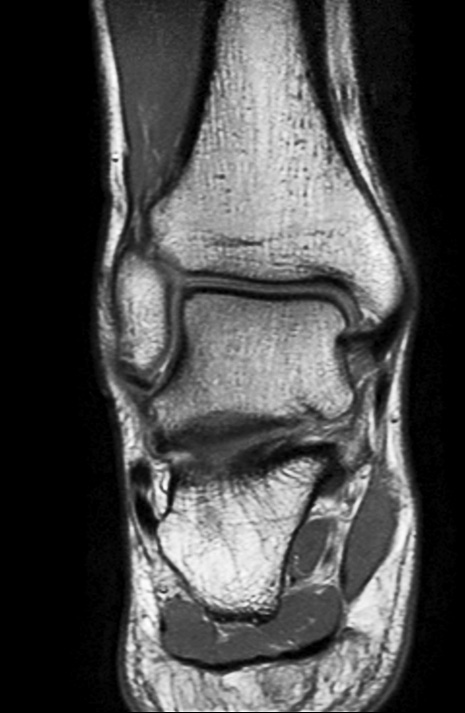

Coronal PDw mDIXON TSE  (water only)